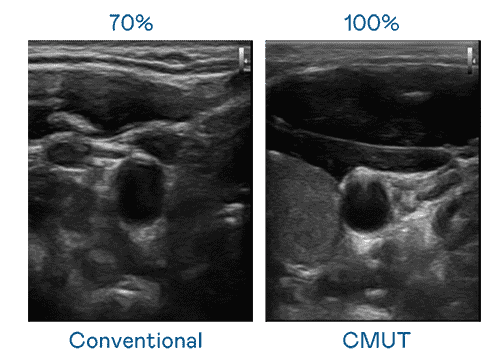

CMUT 技术是一种用电容式微机电元件来产生超音波讯号的技术。。。。与传统 PZT 压电式技术相比,,CMUT 频宽增加 30%,,更宽频的超音波讯号让影像解析度大幅提升,,,,是实现高影像品质医疗超音波扫描、、、促进精准医疗发展的关键技术。。

大频宽带来超清晰影像

超音波影像的解析度高低,,,首先取决于探头能发出的讯号频宽。。。欧陆注册 CMUT 可提供高清晰的超音波讯号,,,提供高频宽、、、、高灵敏度、、、影像纹理细节更高的超音波影像,,,,协助医护人员缩短影像判读时间及利用精准的医疗影像进行诊断。。。